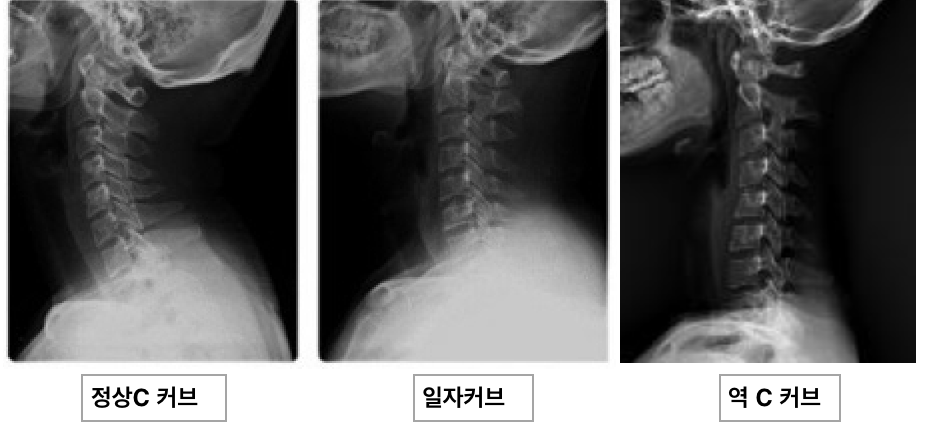

거북목은 얼굴이 앞으로 나오면서 목의 정상 커브인 c자 커브가 사라지면서 일자커브나 역커브의 형태로 변하고 어깨는 말리고 등은 굽는 특징적인 자세 패턴을 의미합니다.이처럼 일자목, 전방두부자세, 굽은 등과 연관된 거북목은 잘못된 자세 습관에 발생하는 대표적인 질병입니다.